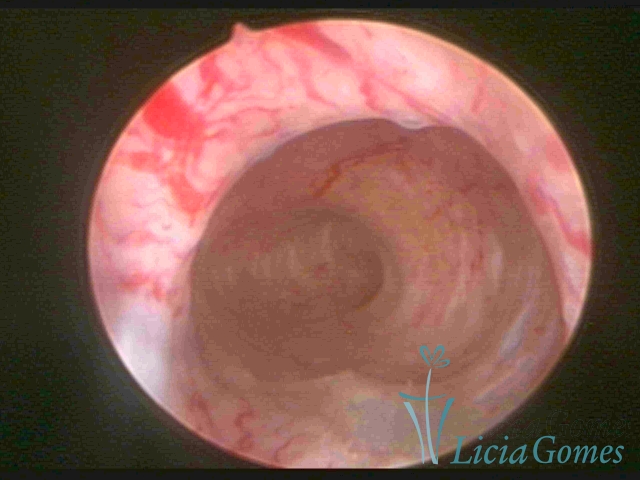

Septate uterus

It probably occurs by the lack of resorption on the middle line, in the merge of Müllerian ducts. The uterus is divided by a partial or total septum which is viewed as a crossbar, not covered by endometrium, which not bleeds when sectioned.

Complete septum when it occupies the whole extension of the cavity, dividing it into two hemicavities.

When this septum occupies only a part of the extension of the uterine cavity, it is considered as incomplete.